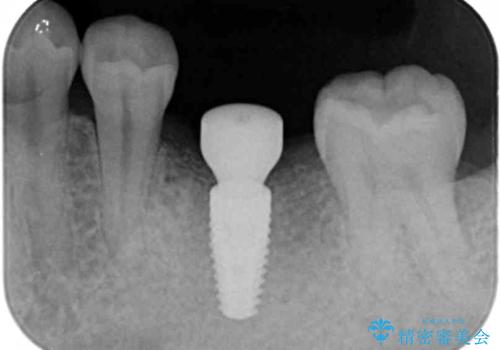

インプラントによる咬合機能回復

- 「長年虫歯放置した結果、抜歯となってしまった左下奥歯に歯を入れたい」、と希望され来院されました。

前後の歯は虫歯も治療歴もないため、前後の歯を削らなくてはいけないブリッジではなくインプラント治療による咬合機能回復を計画します。

- 46.2万円(仮歯・ストローマンインプラント・チタンカスタムアバットメント・ジルコニアクラウン)費用は治療当時の料金となります

減ってしまった顎骨に増骨処置を行うことで、より安定した環境で長く使用できるようなインプラント治療を行っています。